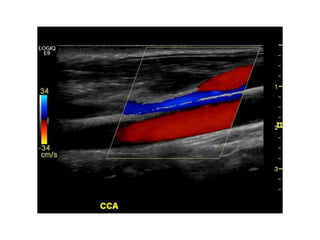

Doppler modes

Color Flow (CF)

A Primer ofDiagnostic Ultrasonic Imaging Modalities Doppler modes: Color Flow (CF) Spectral Doppler

A Primer ofDiagnostic Ultrasonic Imaging Modalities Doppler modes Color Flow (CF)